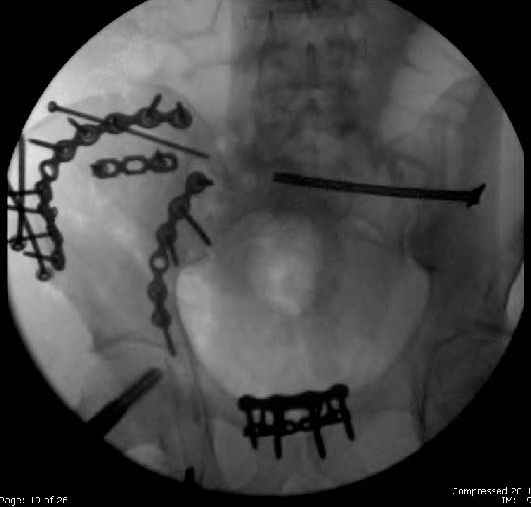

Here are the postop fluoros.

First exposed symphysis & clamped w/Faraboeuf as close to anatomic as possible.

Then extended to R ilioinguinal,really just the lateral window.

Reduced the triangular wedge piece of iliac wing to posterior intact ilium (crescent), held w/k-wire, then used 3-hole push plate to keep from moving, lagged from lat-med w 3.5 screw.

Then 6-hole plate along brim with 1 screw in R sacral ala. Then lagged 2 screws along crest A --> P. finally 10-hole plate along inner aspect of crest. R posterior ilium still a bit stepped off.

Symphysis then 'fine-tuned' & reduced as close as possible to anatomic (but, still with forward rotation of R hemipelvis - or, is it extension?) Accepted that amount of deformity and plated symph

with 4-hole symphyseal plate.

Fluoroed L SI joint and it seemed stable, but wide. So, applied c-clamp to try to squeeze down L SI joint (and note, on the last slide attached, that it's still wide), and got it closer. Single perc Iliosacral screw 40mm thread.

Applied second plate anteriorly on symphysis as I wasn't confident L SI was as stable as it could be and wanted to protect it better.

Thoughts? Thanks for the advice, it's appreciated.